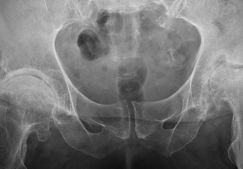

Коксартроз приводит к операции тазобедренного сустава всегда

Операция при коксартрозе тазобедренного сустава 3 и 4 степени. Лечение без операции. Новые методы. Видео и стоимость. Реабилитация. Отзывы.